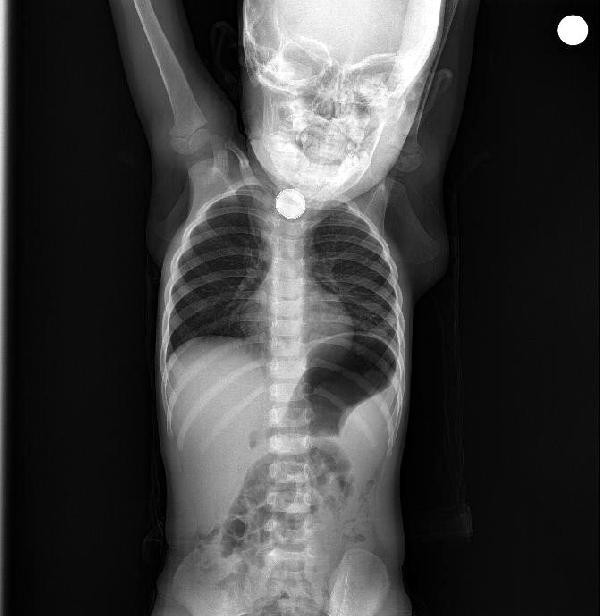

BATMAN’da, Sevim-İbrahim Ramazanoğlu çiftinin kusma ve ishal şikayetiyle hastaneye götürdüğü kızları Berfin’in (1,5) yassı pili yuttuğu belirlendi. Berfin’in boğazının alt kısmındaki pil, operasyonla alındı.

Batman’da yaşayan Ramazanoğlu çifti, bulantı, iştahsızlık ve ishal beliren kızları Berfin’i Batman Devlet Hastanesi’ne götürdü. Doktorun muayene ettiği Berfin’in yemek borusunda cisim tespit edildi. Bunun üzerine Berfin, Elazığ Fırat Üniversitesi Hastanesi’ne sevk edildi. Burada yapılan kontrolde yassı pil yuttuğu tespit edilen Berfin, ameliyata alındı.

Küçük kızın boğazının alt kısmındaki pil, başarılı operasyonla çıkarıldı. Ramazanoğlu çifti ise kızlarının, yaklaşık 3 ay önce yerde oynarken, bir cisim yuttuğunu hatırlayınca, pil yutmuş olabileceğini söyledi.

Operasyonu gerçekleştiren Tıp Fakültesi Çocuk Gastroenteroloji, Hepatoloji ve Beslenme Bilim Dalı Başkanı Prof. Dr. Yaşar Doğan, "Tanı amaçlı yaptığımız endoskopi neticesinde, Berfin'in, yassı bir pil yuttuğunu belirledik. Pili çıkardıktan sonra uzun süre orada kalmasından dolayı yemek borusunda ciddi yanıklar meydana gelmişti.

Hatta bu yanıklar neredeyse nefes borusuyla birleşecek şekilde bir oluşuma gidecekti. Hastamız şu an sağlığına kavuştu. Kliniğimizde şu an oral beslenmeye geçildi. Yarın taburcu etmeyi düşünüyoruz. Yine takiplerimiz devam edecek" dedi.